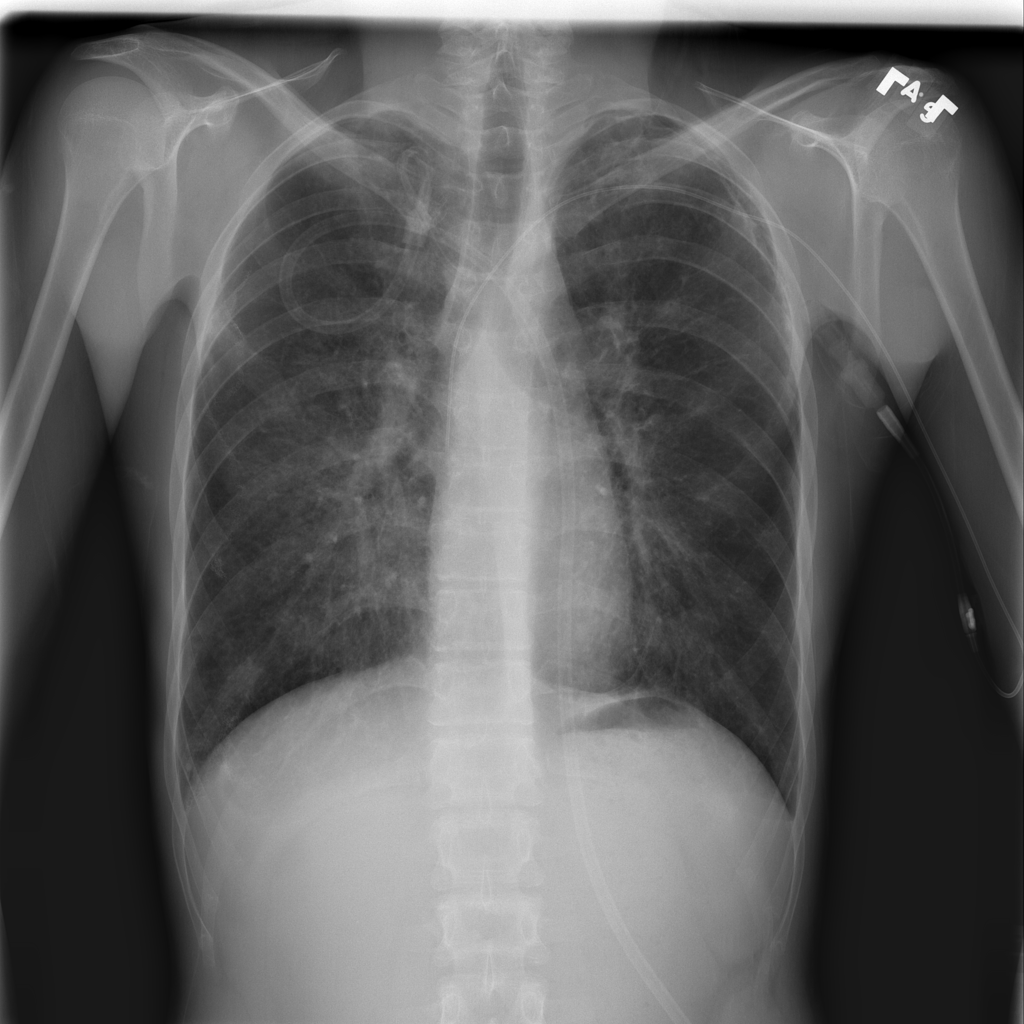

PAT-4639 · IMG-012Pneumothorax

PAT-4639 · IMG-012

AP